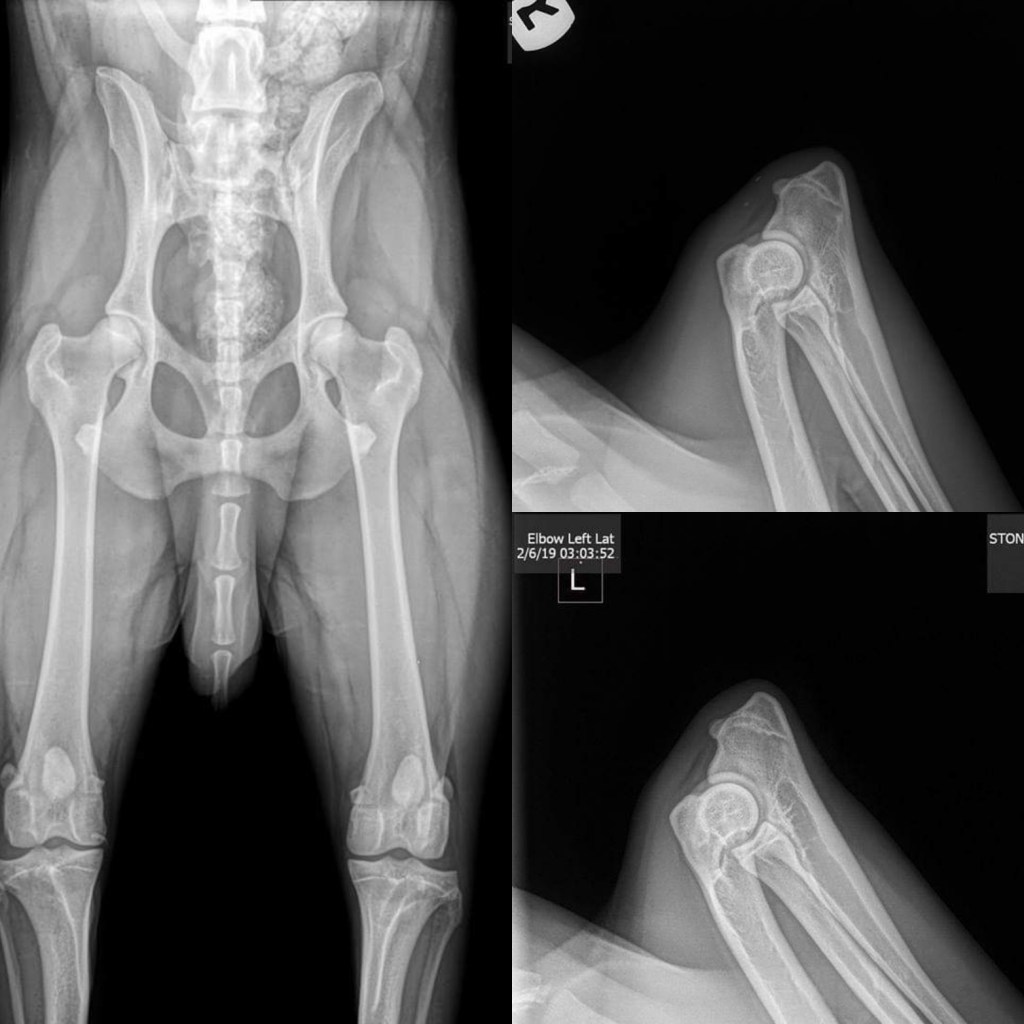

OFA results